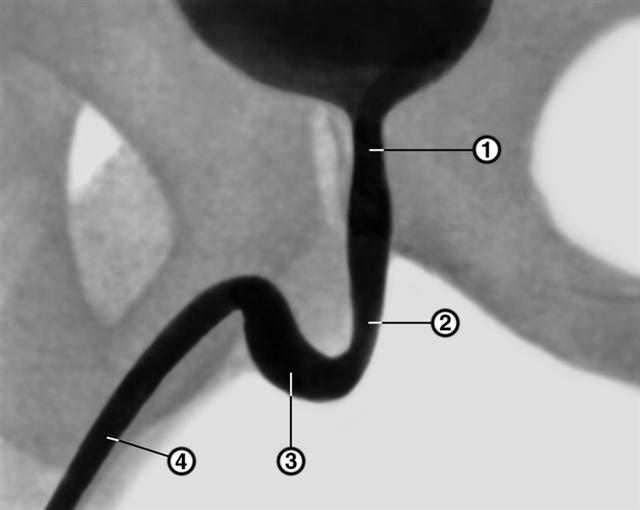

Рис. 1. Нисходящая уретроцистограмма в норме: 1 — предстательная часть уретры; 2 — перепончатая часть; 3 — луковичная часть; 4 — губчатая часть.